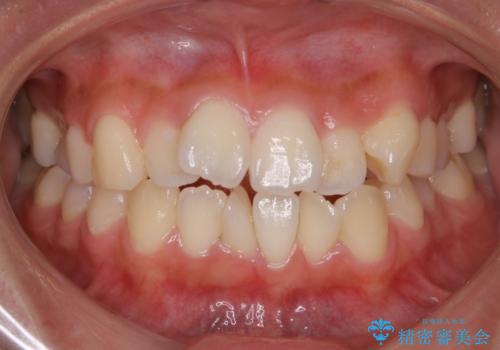

- 上下の歯のガタつきを主訴にご来院されました。

前歯部に特にガタつきが見られ、正中もズレている状態でした。

術前・術後の笑った時の歯の見え方の変化にも注目してみてください!